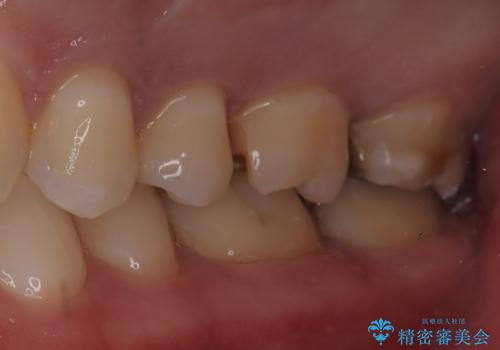

【セラミックインレー】歯科検診にて虫歯発見。

- 定期健診にて虫歯を見つけたためセラミックインレーにて修復しました。

綺麗に仕上がり患者さんも非常に満足されていました。

当院でのセラミックインレーはラバーダム防湿をして接着しております。